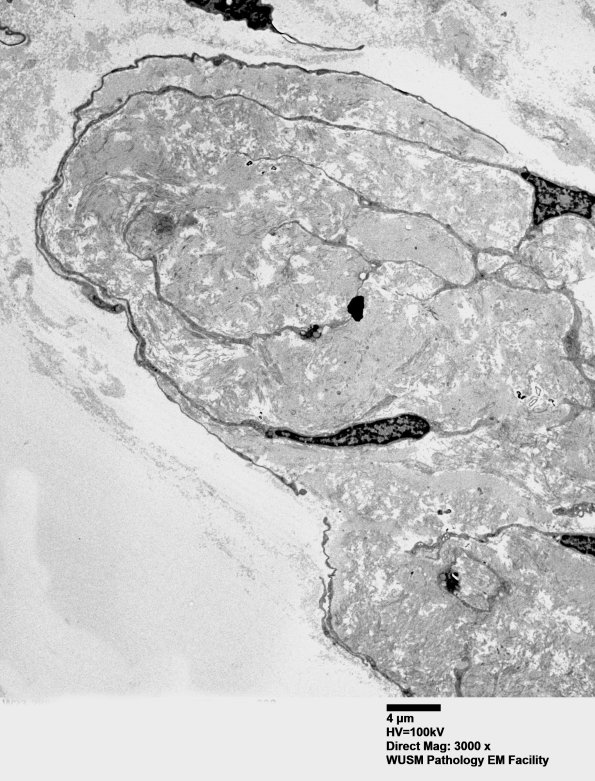

2H10,11 Another RB with a fibroblast-like-cell at two magnifications. (electron micrographs)